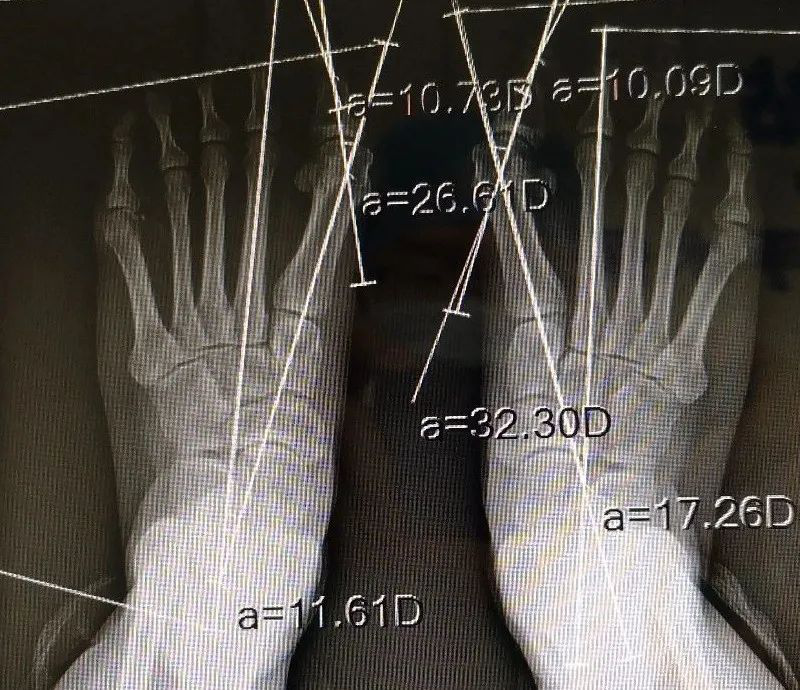

术前进行畸形角度的测量,制定确切的方案。

检查完善后明确了Mcbride+Scarf+Akin术